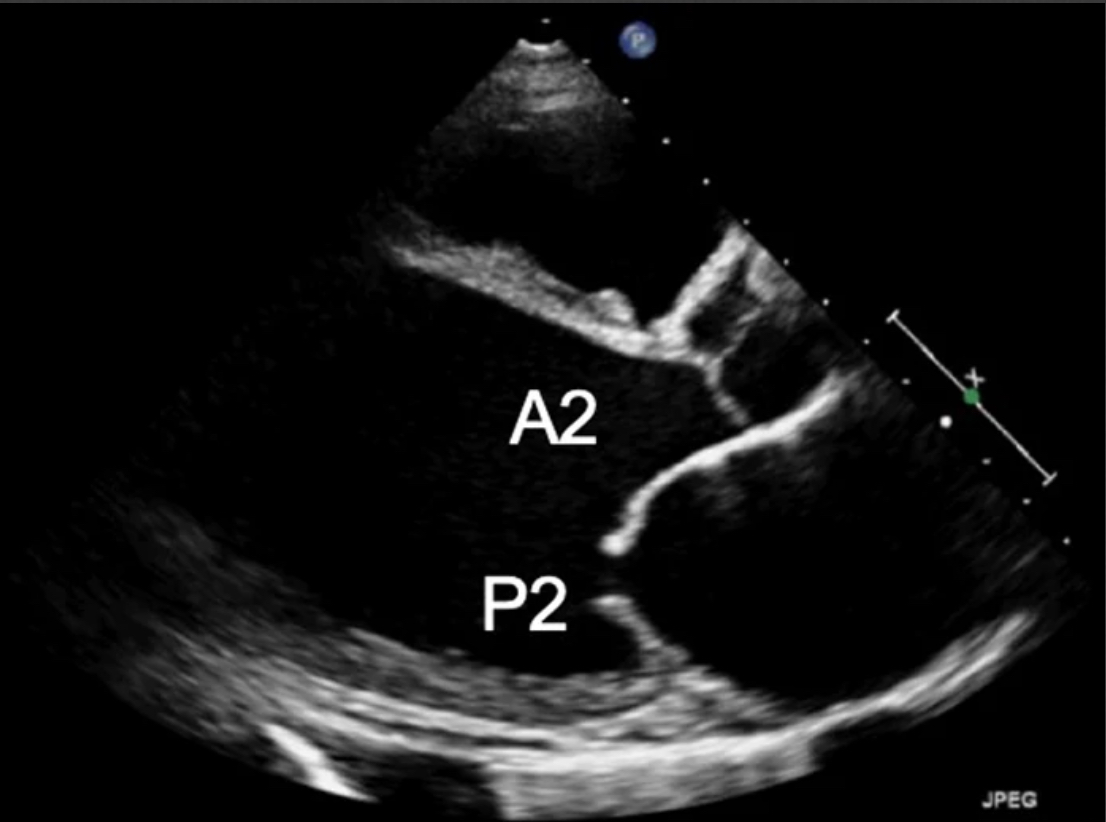

My doc slows down and really looks at the valves.

There it is. An echogenic, mobile structure on the mitral valve, moving with each beat.

The valve is failing — causing torrential mitral regurgitation.

💡 Eureka moment :

This is acute severe MR, likely from papillary muscle rupture → cardiogenic shock.

Let’s talk a bit about mitral valve anatomy.

The mitral valve has two leaflets, divided into six scallops:

Anterior leaflet: A1, A2, A3

Posterior leaflet: P1, P2, P3

All anchored to the mitral annulus.

Disruption of any part of this complex can lead to mitral regurgitation.

Let’s start with 2D imaging.

PLAX & PSAX are your go-to views for mitral valve assessment.

Look carefully for:

• Flail leaflets

• Ruptured papillary muscles

• Prolapse

• Vegetations (IE)

💡 Pro tip:

In PLAX, tilt the probe slightly to visualise different MV scallops — subtle pathology often hides there.

#POCUS #ScanuaryImage